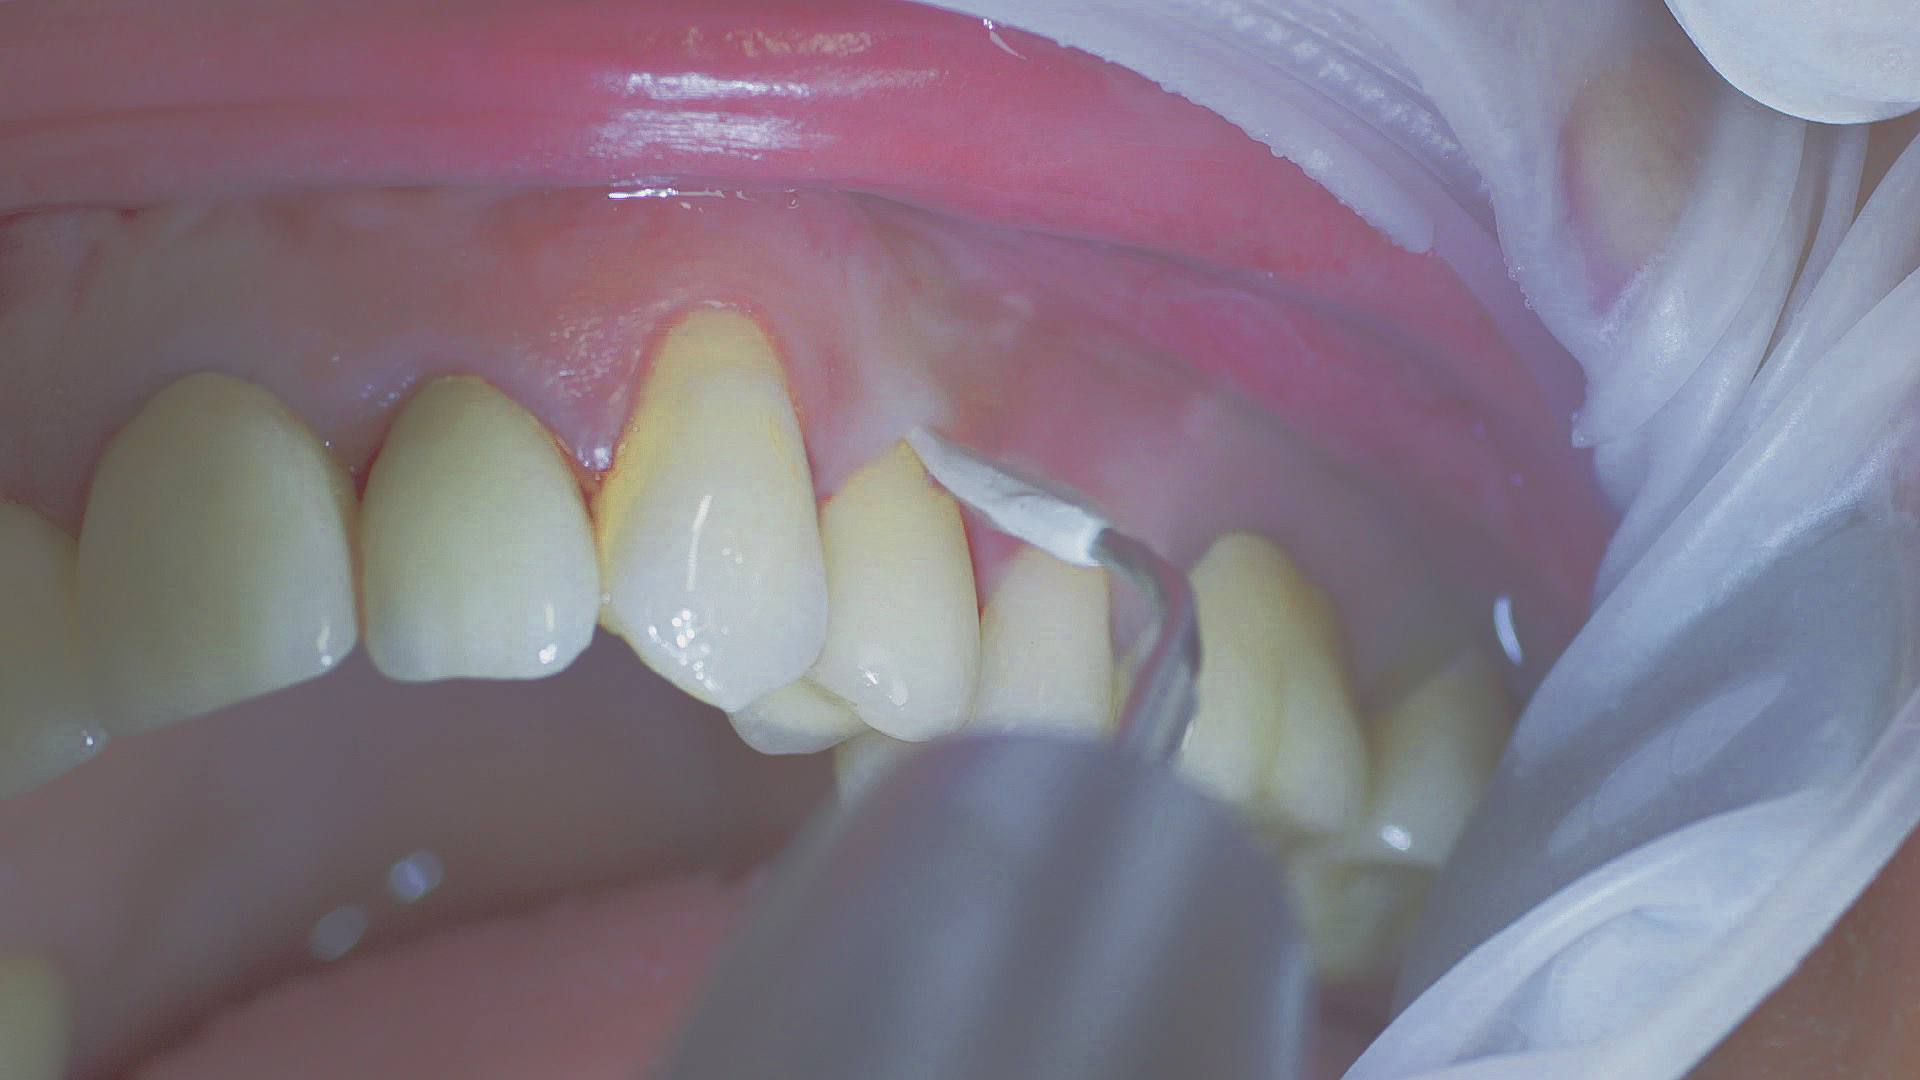

First probe, then treat

Healthy peri-implant tissue does not show any signs of redness, swelling or bleeding, neither does it secrete pus when probed.[5] Based on the consensus document, Prof. Giovanni Salvi explained the importance of regu- lar probing — preferably with a flexible probe, as implant components often tend to obstruct the procedure.[5] In the case of mucositis or initial peri-implantitis already being present, the non-surgical removal of hard deposits and biofilm should be attempted first. For this purpose, ultra- sonic power and special instruments designed to protect the implant should be employed (Fig. 3; piezo scaler Tigon+ with 1I, W&H). In case of no remission, the recall frequency needs to be increased. However, specific recommendations, applicable to individual cases, are not yet available in this context.[15]